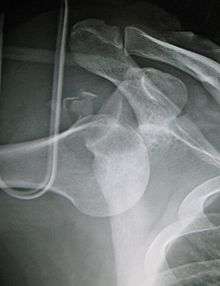

- An anterior dislocation of the shoulder

Anterior dislocation of the right shoulder. AP X ray